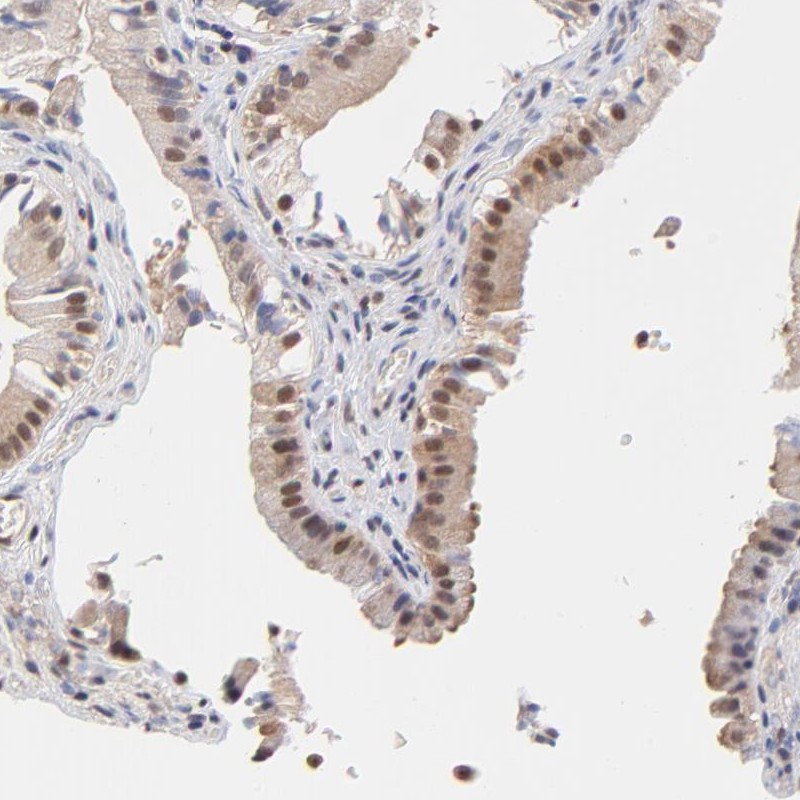

Immunohistochemical staining of human gall bladder shows nuclear positivity in glandular cells.